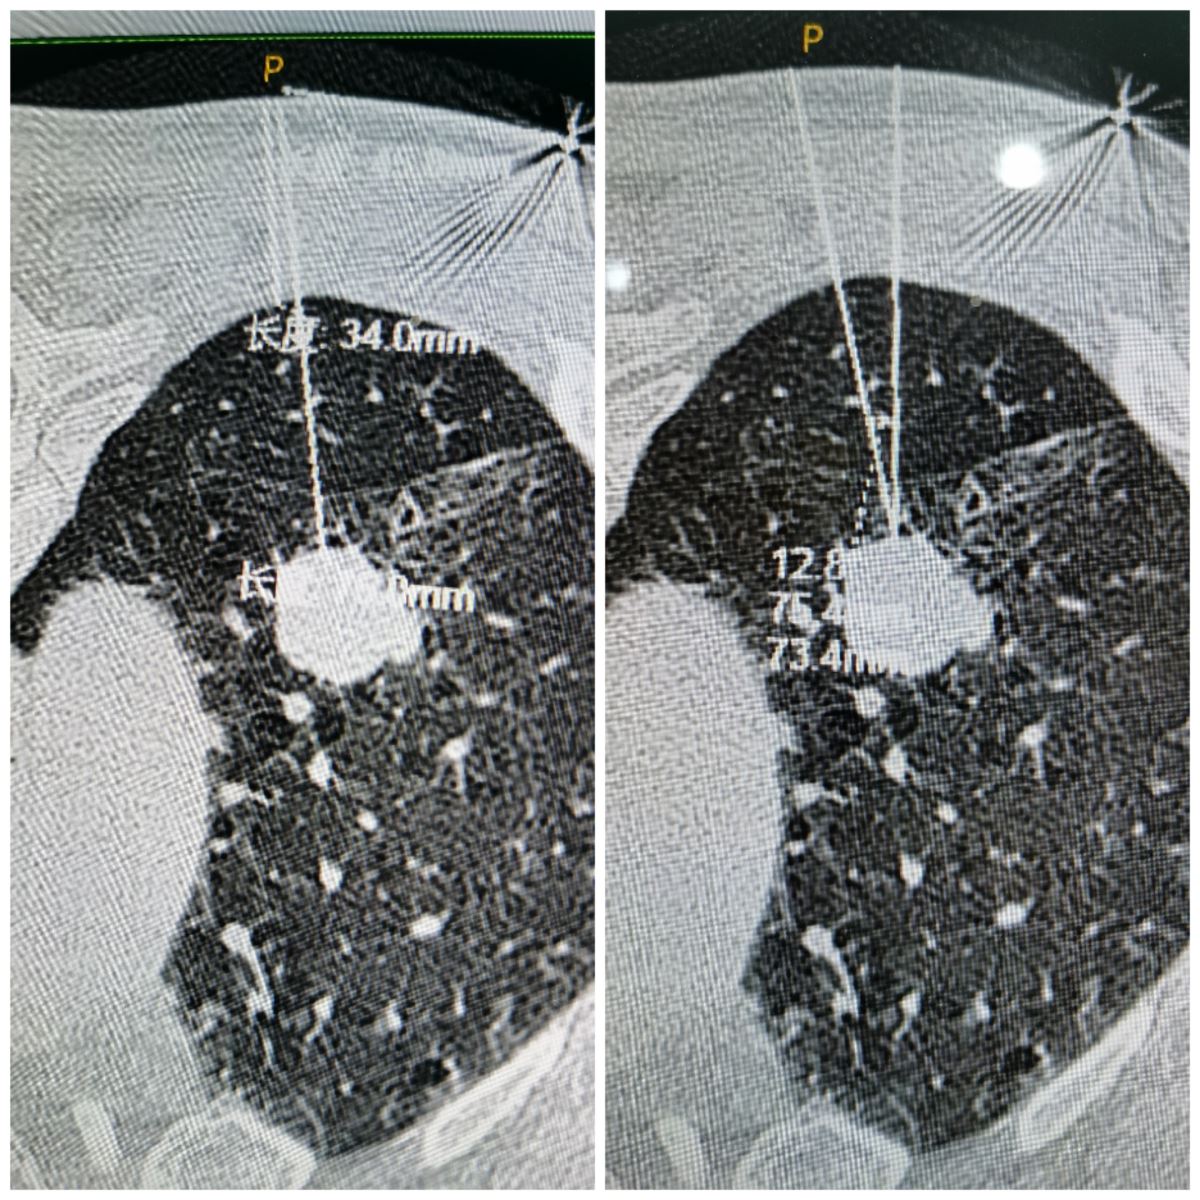

12月11日下午,西院影像科赵海岩、介入科魏东升主任团队共同合作,历时35分钟,成功完成该患者穿刺活检术。首先,测量患者基本体征后进入已消毒CT室,训练吸气、屏气幅度,为后续穿刺准确度做准备;其次,进行胸部CT平扫+增强扫描,根据图像制定穿刺计划,并记录数值;再根据CT定位线及体表定位标识确定入针点,消毒、局麻,根据计划深度,达胸膜外进行胸膜外麻醉,进行CT扫描确认针尖与靶区关系;最后,确认进针方向无误后,引导针进入计划深度,达靶边缘。重复扫描确认针尖位置,退出引导针芯,推出活检针针芯,重复扫描确定针芯位置,击发活检针,取出标本一条。重复上述操作,取出三条标本,送检病理科。